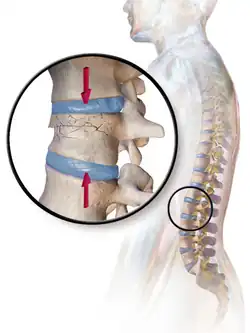

- Compression fracture/wedge fracture – usually occurs in the vertebrae, for example when the front portion of a vertebra in the spine collapses due to osteoporosis (a medical condition which causes bones to become brittle and susceptible to fracture, with or without trauma)

- Burst fracture – in which a vertebra breaks from a high-energy axial load

- Compression fracture – a collapse of a vertebra, often in the form of wedge fractures due to larger compression anteriorly

- Chance fracture – compression injury to the anterior portion of a vertebral body with concomitant distraction injury to the posterior elements